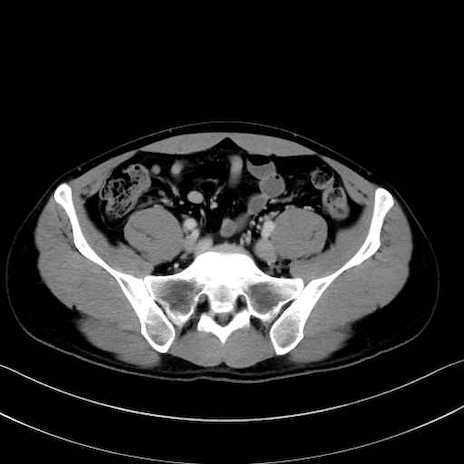

2. 腸腰筋群と骨盤底筋

大腰筋 (Psoas major)

腸骨筋 (Iliacus)